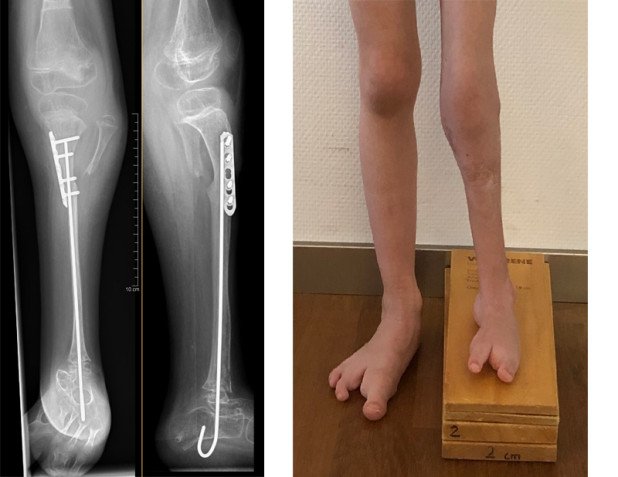

Im Rahmen einer weiteren Operation wurde der Fixateur entfernt und das Wadenbein an den Platz des Schienbeines transferiert. Durch die zuvor durchgeführte Streckung musste das Wadenbein dabei nur wenig verkürzt werden. Damit konnte ein Längenverlust nahezu vermieden werden. Das Mädchen ist heute gehfähig mit einer kleineren Orthese. Das Bein wird aber in Zukunft sicher noch einmal verlängert werden müssen.